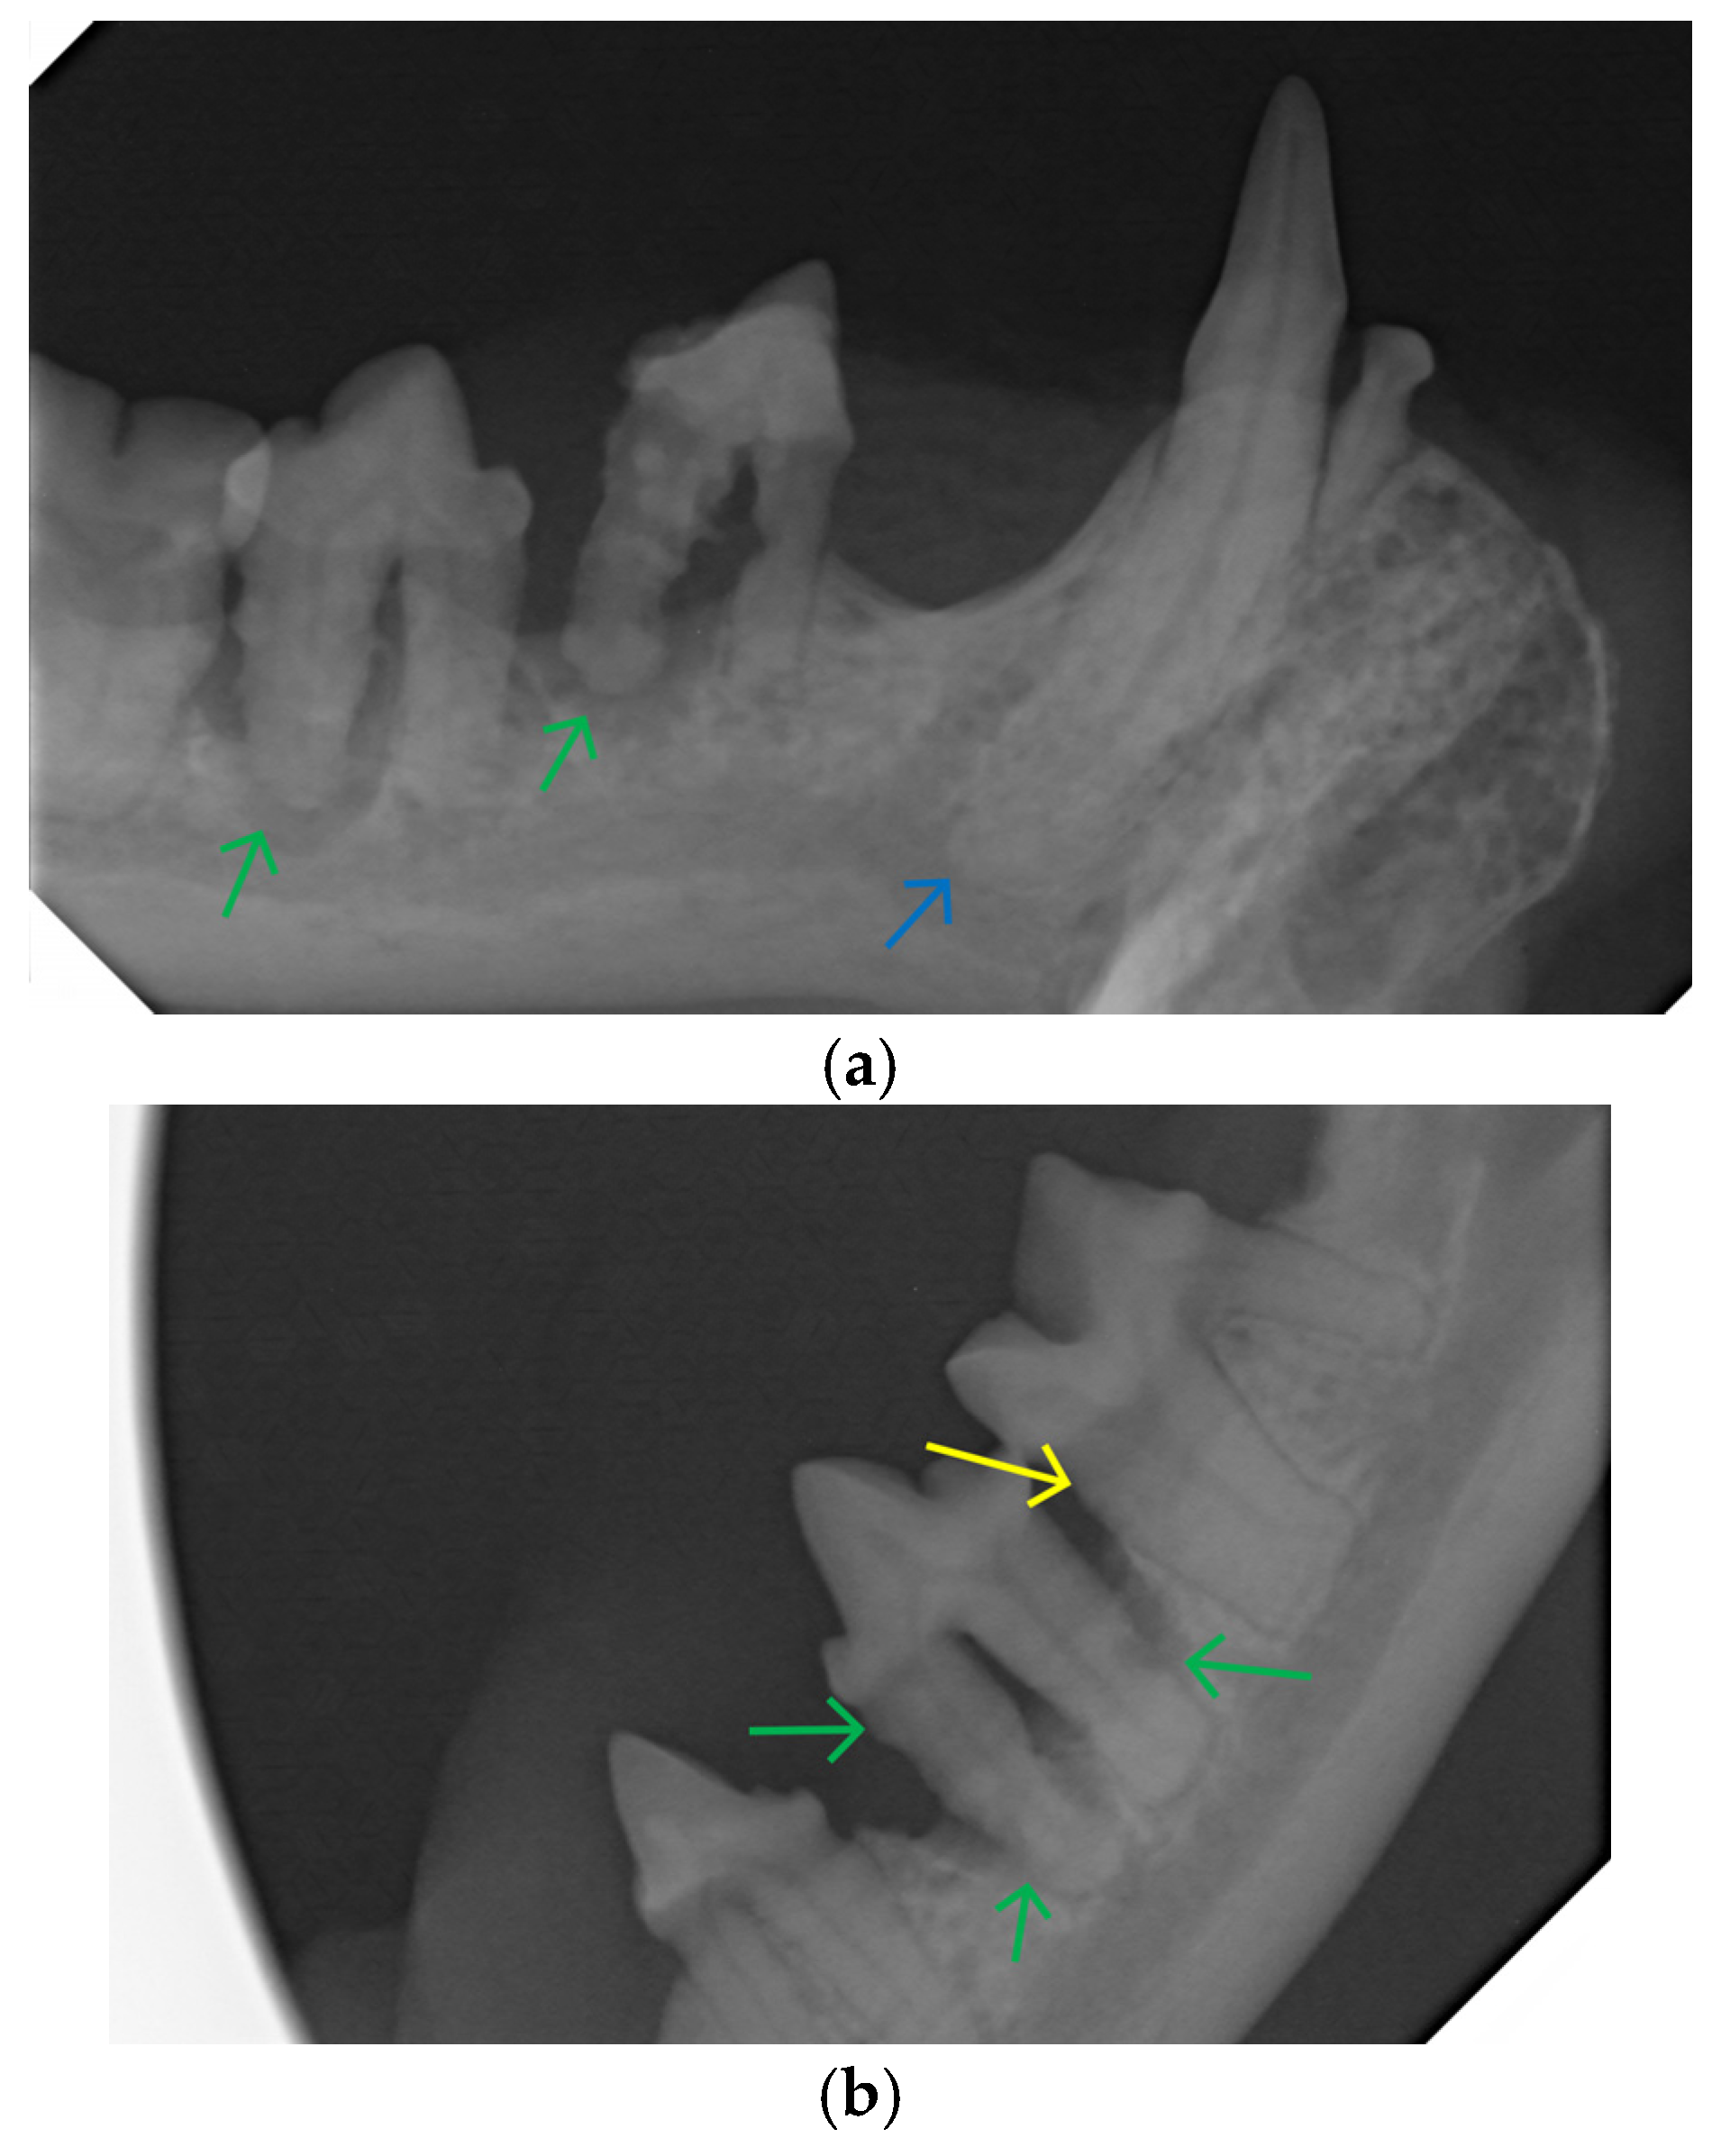

2.2. Dental Examination and Radiography

2.3. Dental Treatment